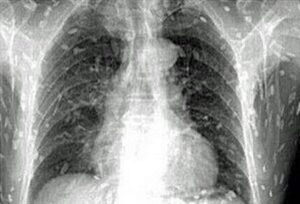

Las larvas de tenia pueden infectar músculos y tejidos blandos. El tejido cerebral puede proporcionar un hogar para las larvas porque es blando y de fácil acceso a través de los vasos sanguíneos. La infección cerebral puede provocar dolores de cabeza, mareos, convulsiones, deterioro cognitivo e incluso demencia, debido a un aumento de la presión del líquido cefalorraquídeo.

Las larvas de tenia pueden infectar músculos y tejidos blandos. El tejido cerebral puede proporcionar un hogar para las…